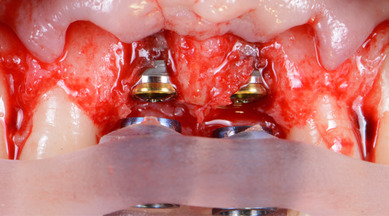

L’objet de cette carte blanche est de proposer une présentation interactive centrée sur des cas cliniques et une approche minimalement invasive.

L’approche minimalement invasive est bien souvent cantonnée à la gestion des tissus mous pour optimiser la cicatrisation. Cet aspect est fondamental et sera abordé au cours de la présentation. Il sera enrichi par une discussion sur cette approche à l’échelle des dents, à travers la problématique de la limite entre conservation et extraction dentaire.